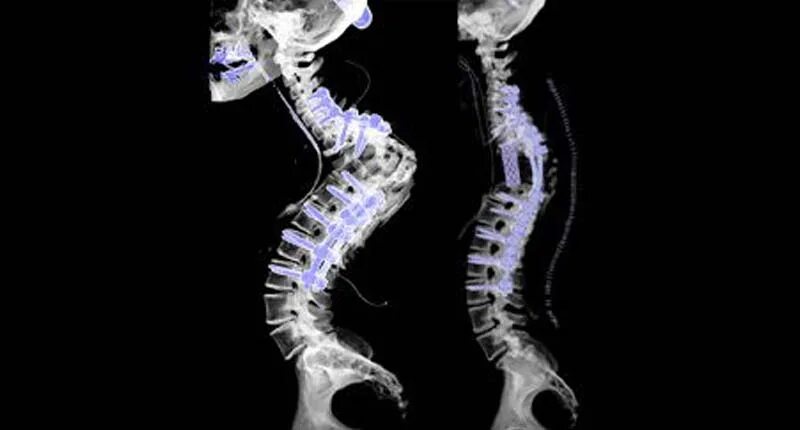

Установка кейджа в позвоночнике